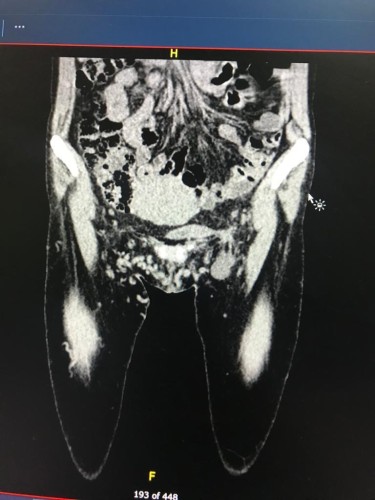

وتفصيلا استقبل المستشفى حالة نادرة من التواء المعدة ، و الذي ادى إلى انفجارها .

و قام اطباء الاشعة بتشخيص الحالة منذ القدوم ، و بناءً على ذلك تقرر اجراء العملية و التي تكللت بالنجاح و تم إخراج المريض بحالة جيدة لمعاودة ممارسة حياته الطبيعية.

كما قام الفريق الطبي بإجراء عملية جراحية لثقب بالاثني عشر ادت إلى التهاب بروتوني حاد ، و تسمم لدى المريض في القلب ، و انسداد بالشرايين ، و بجهود الفريق الجراحي مع طاقم التخدير و العناية تكللت العملية بالنجاح حيث ان الحالة كانت تستدعي خبرات عالية ، و عناية فائقة ، وكذلك القدرة الكاملة علي التعامل مع مثل هذه الحالات الصعبة و الحرجة .